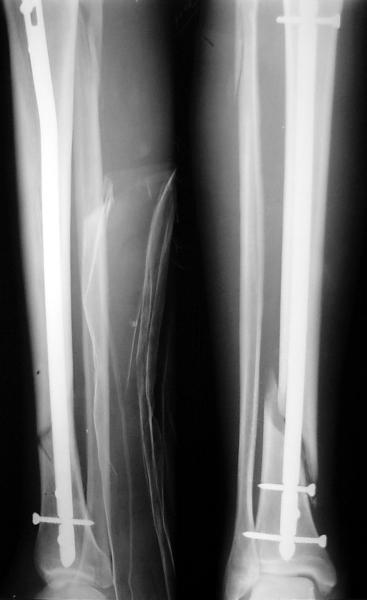

Как мне показать пример? Фото стоящего на одной оперированной конечности пациента? O! Пример, подвигнувший нас на некоторое изменение технологий. Пациент этот ходил с полной нагрузкой вопреки рекомендациям. В качестве подтверждения - сломанный проксимальный статический винт к 1 мес., а к 2 мес. - все остальные. Сейчас мы перешли на более fool-proof остесинтез.

На мой взгляд, на снимках, приведённых Вами - неправильно сростающийся перелом дистальной трети большеберцовой кости, состояние после остеосинтеза интрамедуллярным гвоздём.

Как Вы пишите снимок под номером 1 - менсяц после операции, под номером 2- два месяца после операции.

I think that the X-Rays show S/P IMN of Spiral # of the Distal Tibia consoles in misalignment.

You wrote that a picture number 1 - f month after the surgery, and number 2-two months after the surgery.

Ok. А также и следующий, в 3 месяца.

Это наглядная демонстрация возможности ранней полной нагрузки при нестабильном по оси повреждении, причем не в самых благоприятных механических условиях - при плохом сопоставлении, со слабым фиксатором.